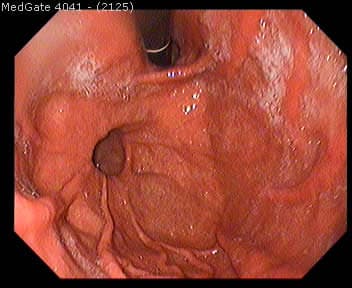

Direkt karın grafileri (röntgen), baryumlu kolon grafisi, anorektal manometrik inceleme ve rektal biyopsi tanı yöntemleri arasındadır.